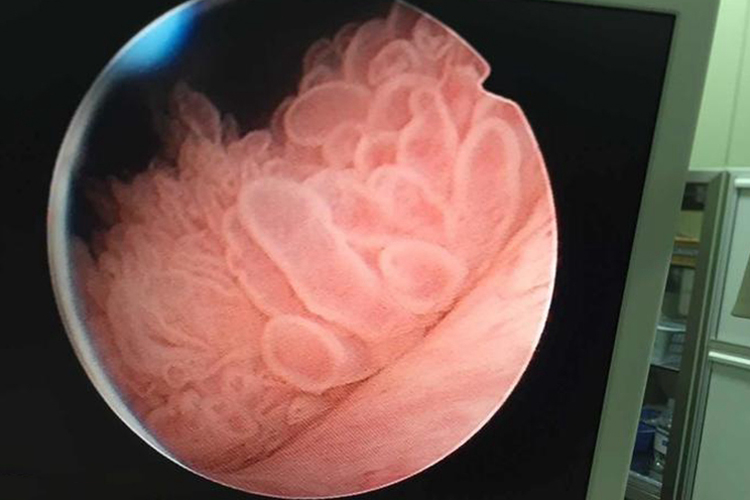

乳头状癌:单发或多发,肿瘤局限在黏膜或黏膜固有层,蒂细长,蒂上长出绒毛状分支,在膀胱内注水时,肿瘤乳头在水中飘荡,犹如水草;结节、团块乳头状癌蒂较粗,乳头分支短而粗,有时像杨梅状,往膀胱注水时活动较少,附近黏膜增厚、水肿。